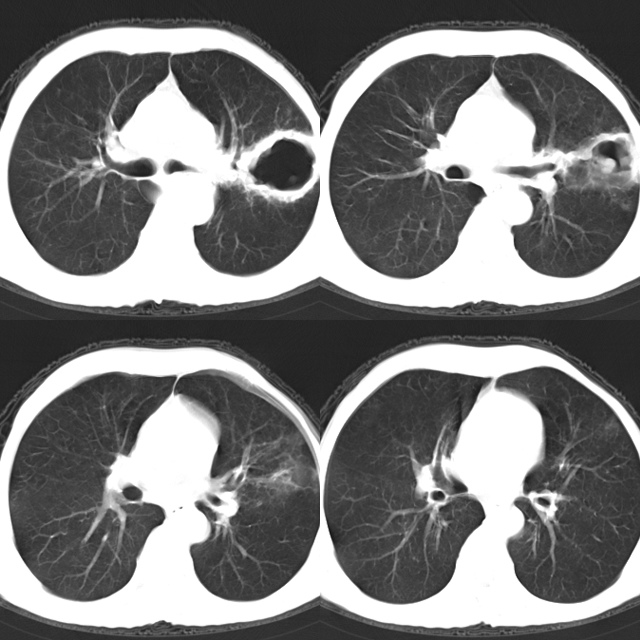

以下是引用心路寻觅在2010-4-17 18:35:00的发言:[br]纵膈多组淋巴结肿大呈“冰冻纵膈”,左肺上叶空洞伴其内结节密度影,考虑淋巴瘤伴左肺上叶曲霉菌感染。[br][br][本贴已被 心路寻觅 于 2010-4-17 18:36:23 修改过]

以下是引用zhangzhongshou在2010-4-17 19:32:00的发言:[br]一元论考虑左肺空洞型肺癌并纵隔淋巴结转移可能性大。